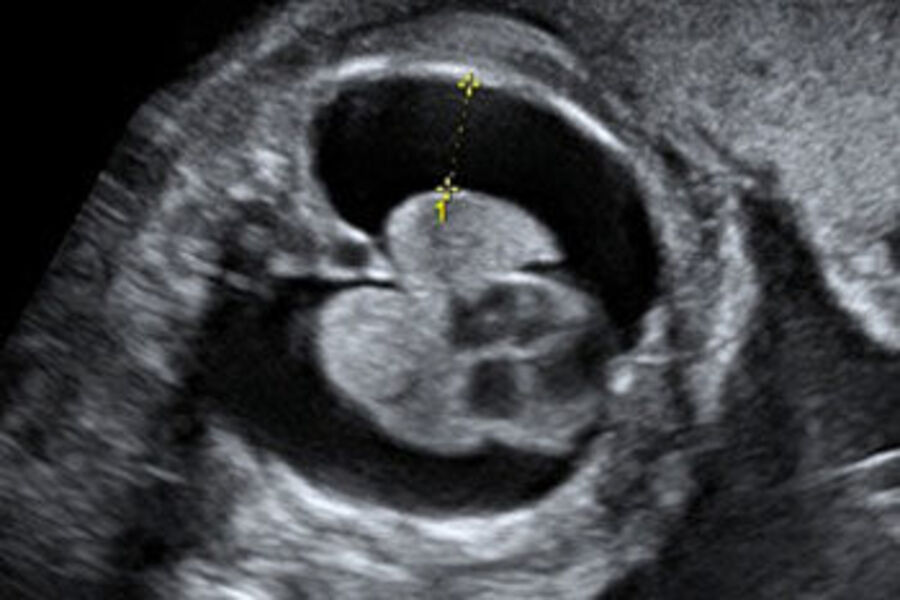

Theo BSCKI. Vương Thị Bích Thủy – Bác sĩ Trung tâm Y học Bào thai, Bệnh viện Đại học Phenikaa (PhenikaaMec), chọc hút dịch màng phổi thai nhi dưới siêu âm là thủ thuật can thiệp bào thai nhằm dẫn lưu lượng dịch bất thường tích tụ trong khoang màng phổi. Thủ thuật được thực hiện bằng kim chuyên dụng, đi qua thành bụng mẹ, tử cung và tiếp cận khoang màng phổi thai nhi dưới sự hướng dẫn trực tiếp của siêu âm.

Việc theo dõi hình ảnh thời gian thực giúp bác sĩ kiểm soát chính xác vị trí kim, lượng dịch được hút ra và kịp thời điều chỉnh thao tác nếu phát hiện bất thường, từ đó hạn chế tối đa nguy cơ biến chứng cho cả mẹ và thai nhi. Can thiệp sớm trong tử cung giúp cải thiện chức năng phổi và tuần hoàn của thai.

BSCKI. Vương Thị Bích Thủy cho biết: “Dưới hướng dẫn của siêu âm, bác sĩ đưa kim nhỏ vào khoang màng phổi thai nhi để hút dịch. Sau can thiệp, thai phụ được theo dõi sát tại bệnh viện từ 24–48 giờ nhằm phát hiện sớm các biến chứng như rỉ ối, co tử cung hay tái tích tụ dịch. Thai phụ cần theo dõi sát theo hướng dẫn của bác sĩ, tái khám đúng hẹn nhằm phát hiện sớm nguy cơ tái tích tụ dịch và đảm bảo an toàn cho thai nhi đến khi sinh.”